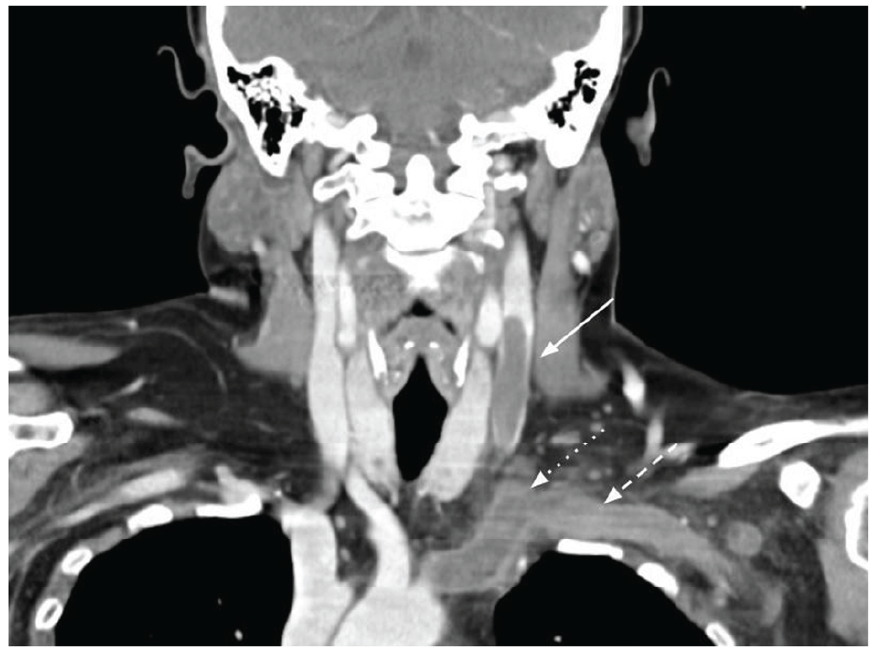

Figura 1: Corte coronal de TC evidenciando volumoso trombo na veia jugular interna (seta cheia), com extensão ao tronco braquiocefálico (seta em picotado) e veia subclávia (seta em tracejado).

Mulher de 47 anos, diagnosticada com lúpus eritematoso sistémico (LES) de atingimento articular (artralgias a nível cervical, dorsal, ombro, cotovelo, punho e joelhos) e cutâneo (rash malar ocasional), medicada com hidroxicloroquina, azatioprina e deflazacorte. Apresentava controlo sintomático adequado e níveis de complemento normais, quando desenvolveu cervicalgia esquerda não desencadeada pelo esforço, palpitações e cansaço, com uma semana de evolução. Posteriormente desenvolveu edema cervical, motivando ida ao serviço de urgência. À admissão, encontrava-se eupneica, taquicárdica, hipertensa, sem alterações à auscultação cardiopulmonar. Objetivado exuberante edema cervical com extensão ao ombro esquerdo, doloroso ao toque, sem enfisema, e notório engorgitamento venoso na região torácica esquerda. Analiticamente apresentava d-dímeros 1378 ng/mL, sem outras alterações. A angiotomografia cervical revelou um volumoso trombo (6 cm) na veia jugular interna (VJI) esquerda, com extensão à veia subclávia e tronco braquiocefálico (Fig. 1). A doente foi internada no serviço de Medicina, verificando-se evolução favorável após início de hipocoagulação com enoxaparina, posteriormente alterada para varfarina por eventual síndrome do anticorpo anti-fosfolípido (SAAF) secundário ao LES.1,2